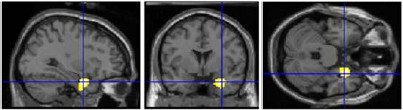

2) beautiful images activated right amygdala (responds to learned emotional information): evidence for __________ beauty (“I like that.”)

right amygdala activity